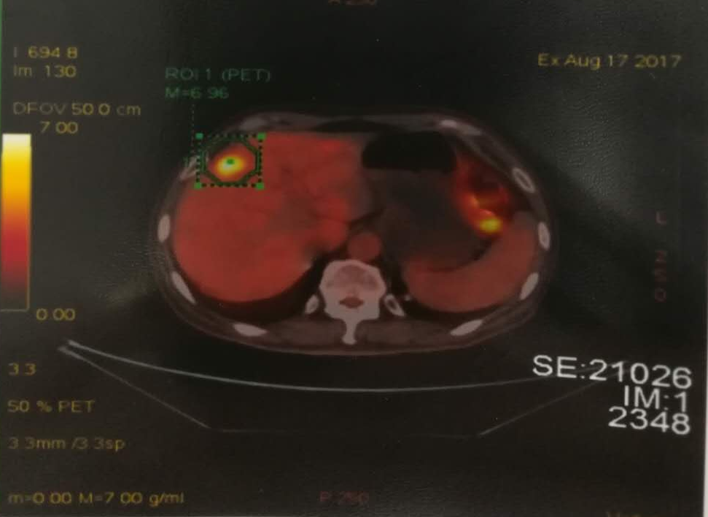

PET/CT结果(2017-08-17)

1、结肠癌术后化疗后,结肠术区见金属吻合器影,周围肠系膜结构稍致密,见斑片索条影,考虑术后改变为主。

2、肝脏内见多发稍低密度影,FDG代谢不同程度增高,结合病史考虑转移可能大。

3、左下肺见片状实变影,FDG代谢轻度增高,结合病史,考虑治疗后改变可能,请结合患者既往老片并密切随访。